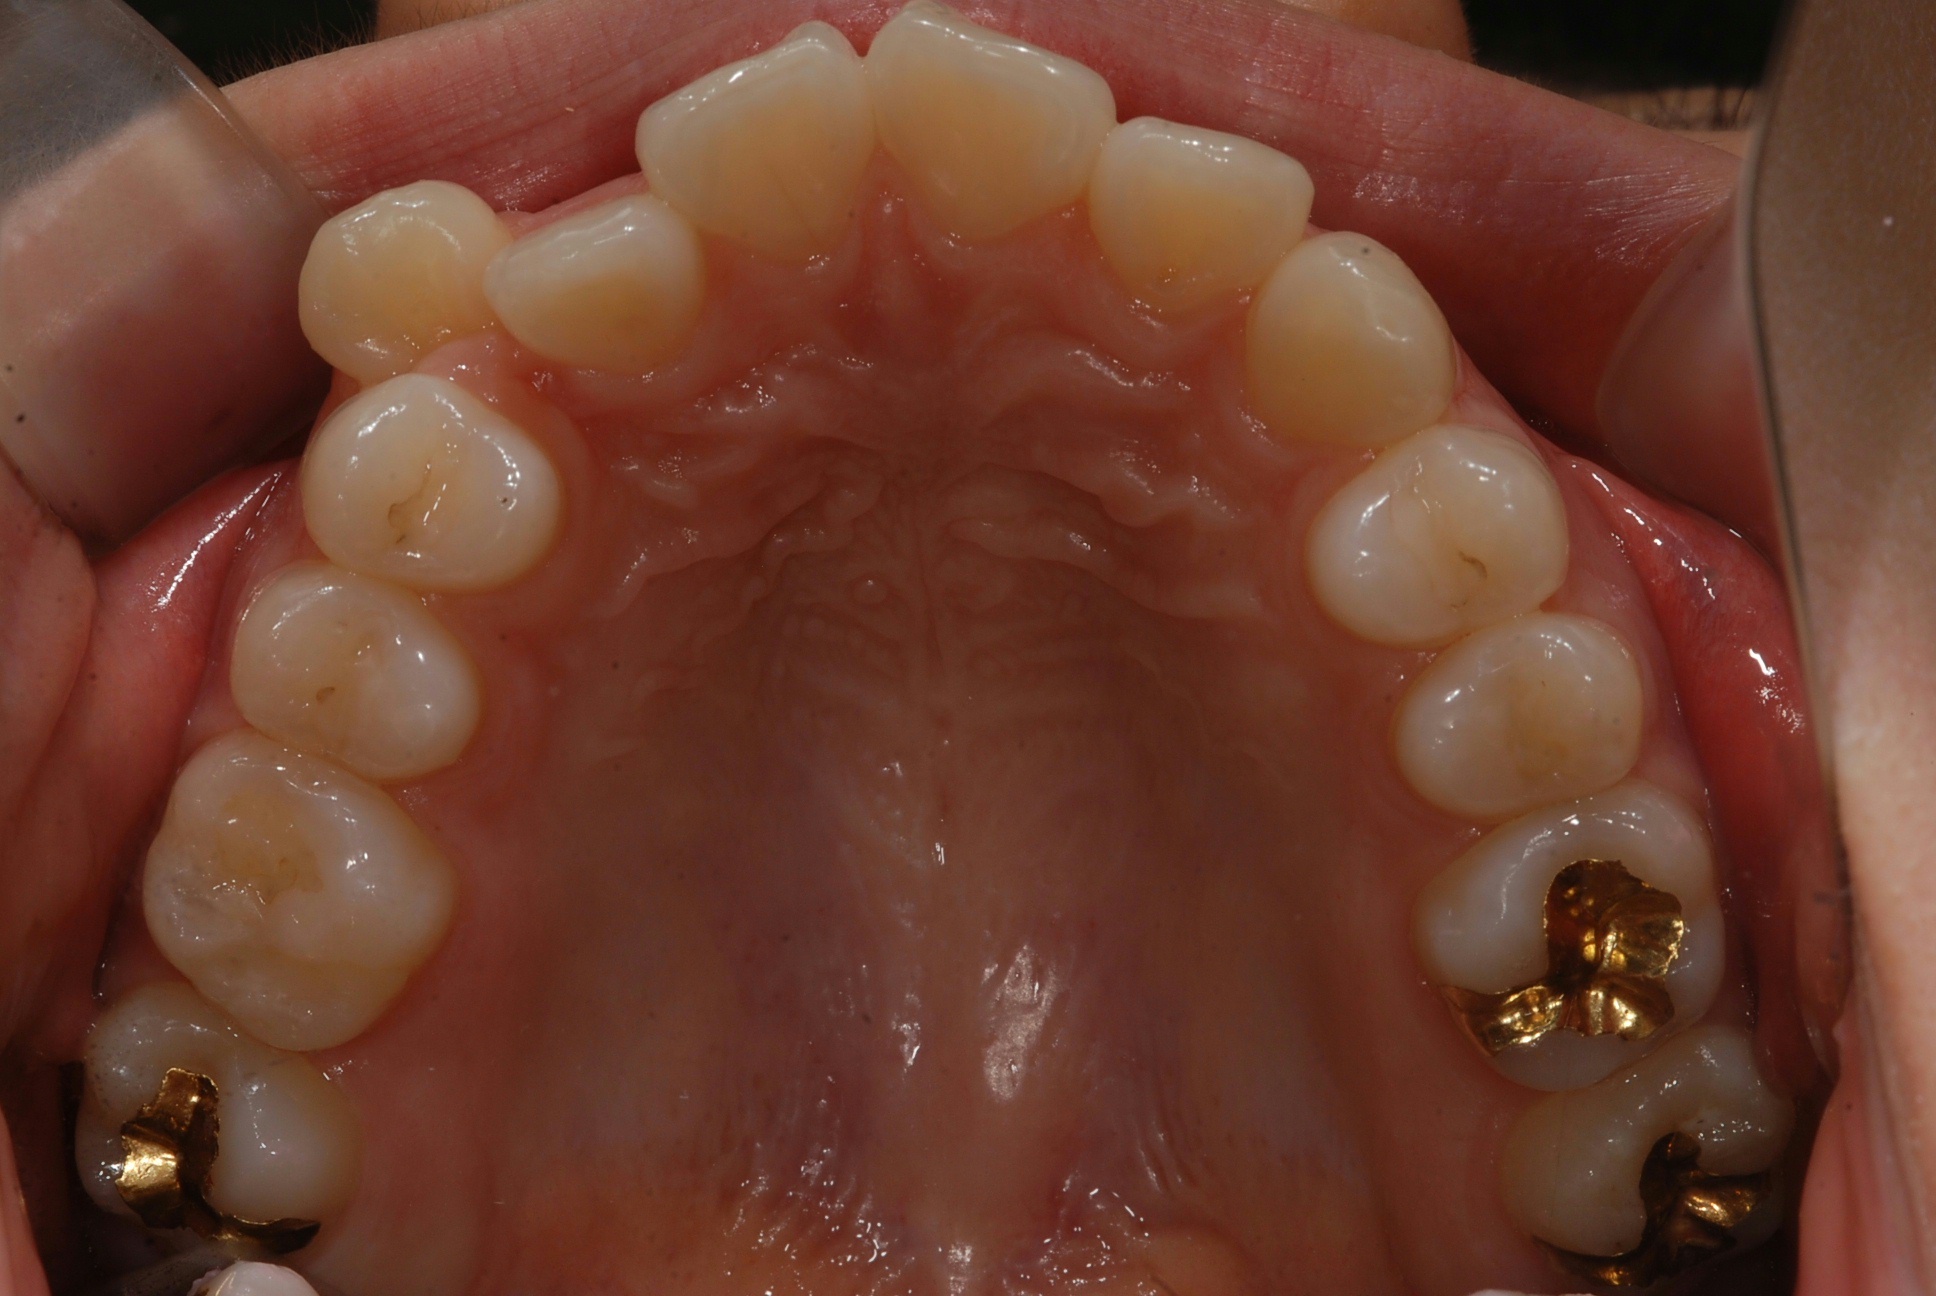

치료 후 사진입니다.